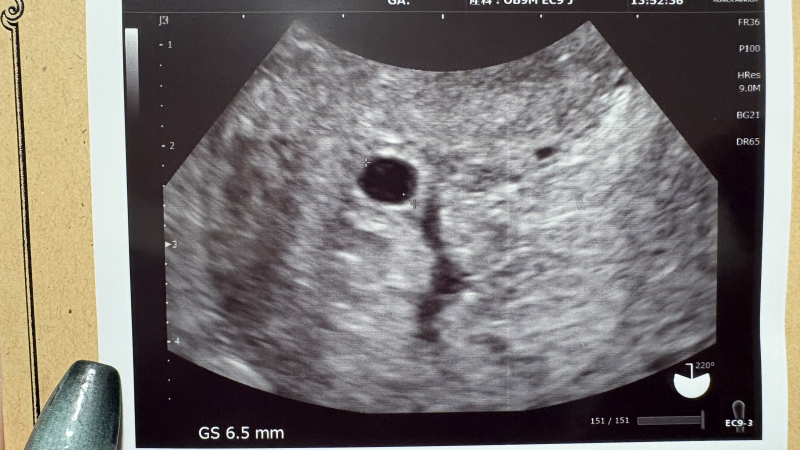

6w5dに産婦人科に行ったところGS6.5mm空っぽの胎嚢のみの確認で2週間後にもう1度来るよう案内がありました。